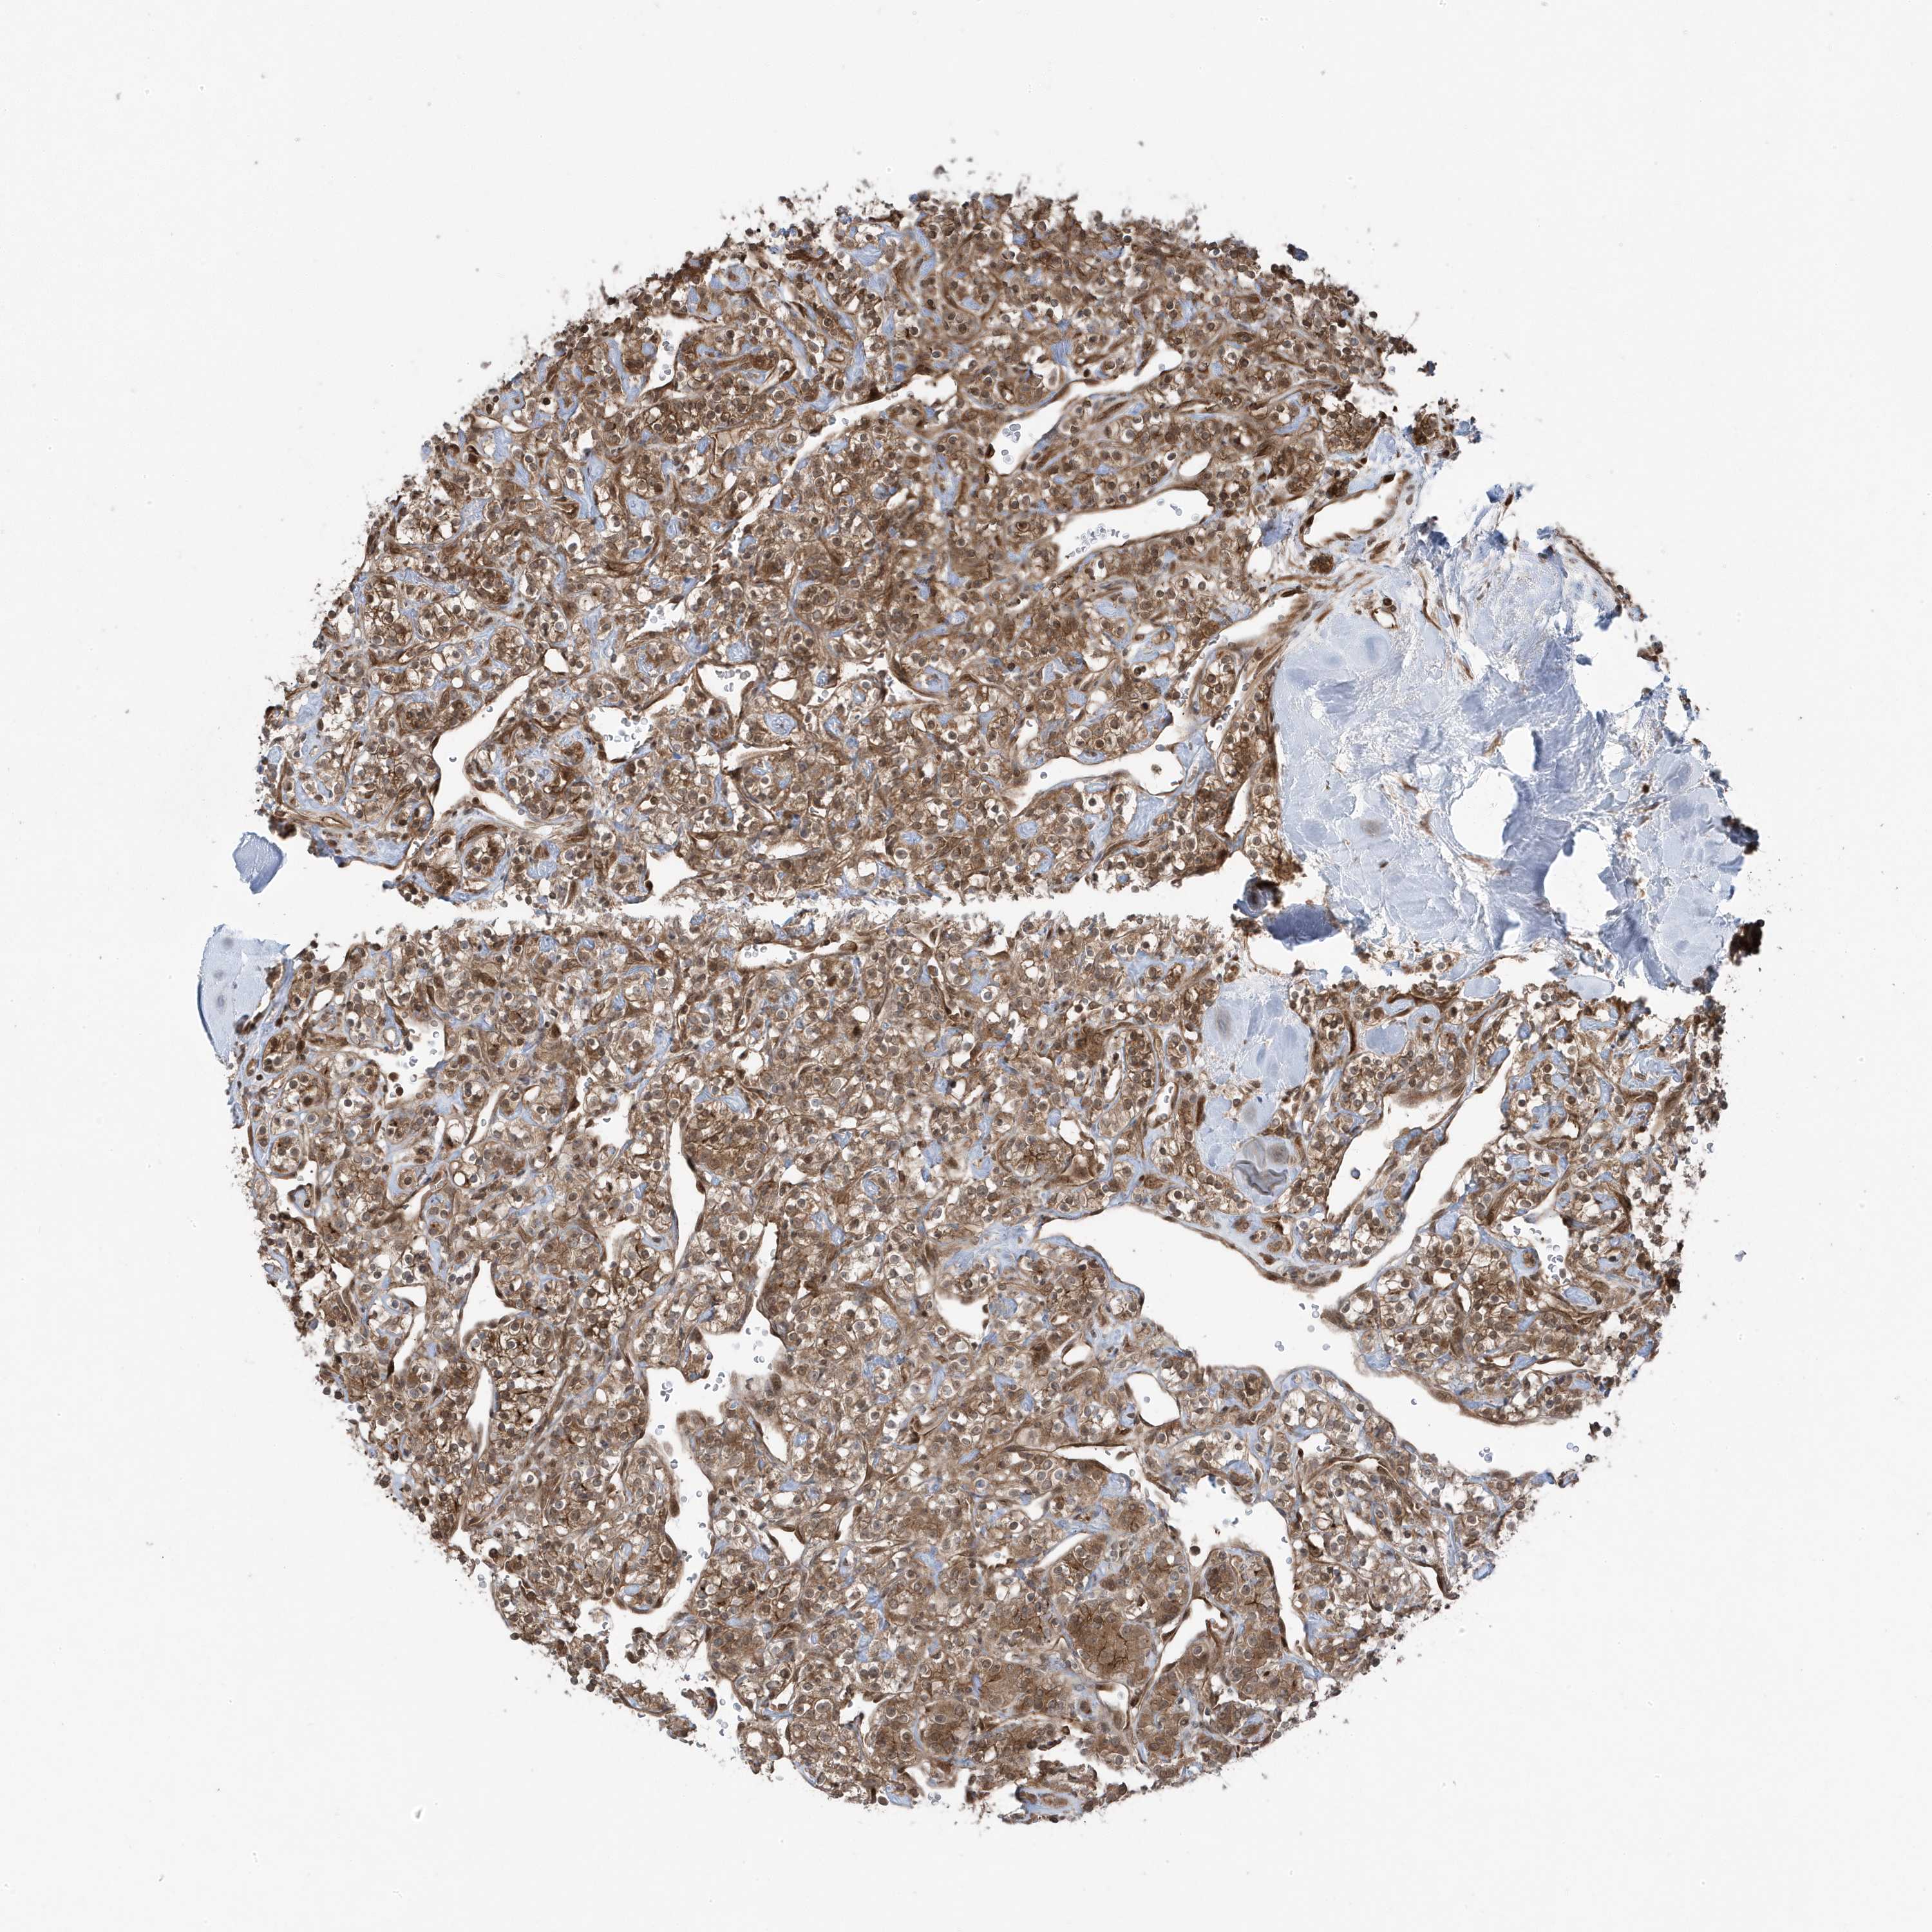

KIDNEY RENAL CLEAR CELL CARCINOMA (TCGA) - Interactive survival scatter ploti

The Survival Scatter plot shows the clinical status (i.e. dead or alive) for all individuals in the patient cohort, based on the same data that underlies the corresponding Kaplan-Meier plots. Patients that are alive at last time for follow-up are shown in blue and patients who have died during the study are shown in red.

The x-axis shows the expression levels (FPKM) of the investigated gene in the tumor tissue at the time of diagnosis. The y-axis shows the follow-up time after diagnosis (years). Both axes are complimented with kernel density curves demonstrating the data density over the axes. The top density plot shows the expression levels (FPKM) distribution among dead (red) and alive patients (blue). The right density plot shows the data density of the survived years of dead patients with high and low expression levels respectively, stratified using the cutoff indicated by the vertical dashed line through the Survival Scatter plot. This cutoff is automatically defined based on the FPKM cutoff that minimizes the p-score. The cutoff can be changed by dragging the vertical line or by entering a cutoff value in the square labeled "Current cut-off".

Under the Survival Scatter plot the p-score landscape (black curve; left axis) is shown together with dead median separation (red curve; right axis). Dead median separation is the difference in median mRNA expression between patients who have died with high and low expression, respectively. It is calculated as follows: median FPKM expression of dead patients with high expression - median FPKM expression of dead patients with low expression. This is intended to aid the user in visually exploring custom cutoffs and the associated p-scores and dead median separation.

Individual patient data is displayed and can be filtered by clicking on one or more of the category buttons on the top of the page. Categories describing expression level and patient information include: high, low, alive, dead, female, male and tumor stages. The scale of the x-axis can be toggled between linear and log-scale by clicking on the "x log" button. Mouse-over function shows TCGA ID, patient information and mRNA expression (FPKM) for each patient.

& Survival analysisi

Kaplan-Meier plots summarize results from analysis of correlation between mRNA expression level and patient survival. Patients were divided based on level of expression into one of the two groups "low" (under cut off) or "high" (over cut off). X-axis shows time for survival (years) and y-axis shows the probability of survival, where 1.0 corresponds to 100 percent.

MAPK1IP1L is potential prognostic, high expression is favorable in Kidney Renal Clear Cell Carcinoma (TCGA)

Best expression cut offi

Based on the FPKM value of each gene, patients were classified into two groups and association between prognosis (survival) and gene expression (FPKM) was examined. The best expression cut-off refers the FPKM value that yields maximal difference with regard to survival between the two groups at the lowest log-rank P-value. Best expression cut-off was selected based on survival analysis .

When clicking on this number, the vertical dashed line indicating cut-off, the interactive survival plot, and the Kaplan-Meier curve will be adjusted to show results based on the best expression cut-off.

: 39.09

TCGA RNA samplesi

RNA-seq data is reported as average FPKM (number Fragments Per Kilobase of exon per Million reads), generated by the The Cancer Genome Atlas (TCGA) .

Normal distribution across the dataset is visualized with box plots, shown as median and 25th and 75th percentiles. Points are displayed as outliers if they are above or below 1.5 times the interquartile range. FPKM values of the individual samples are presented next to the box plot.

Average pTPM 35.1

Number of samples 521